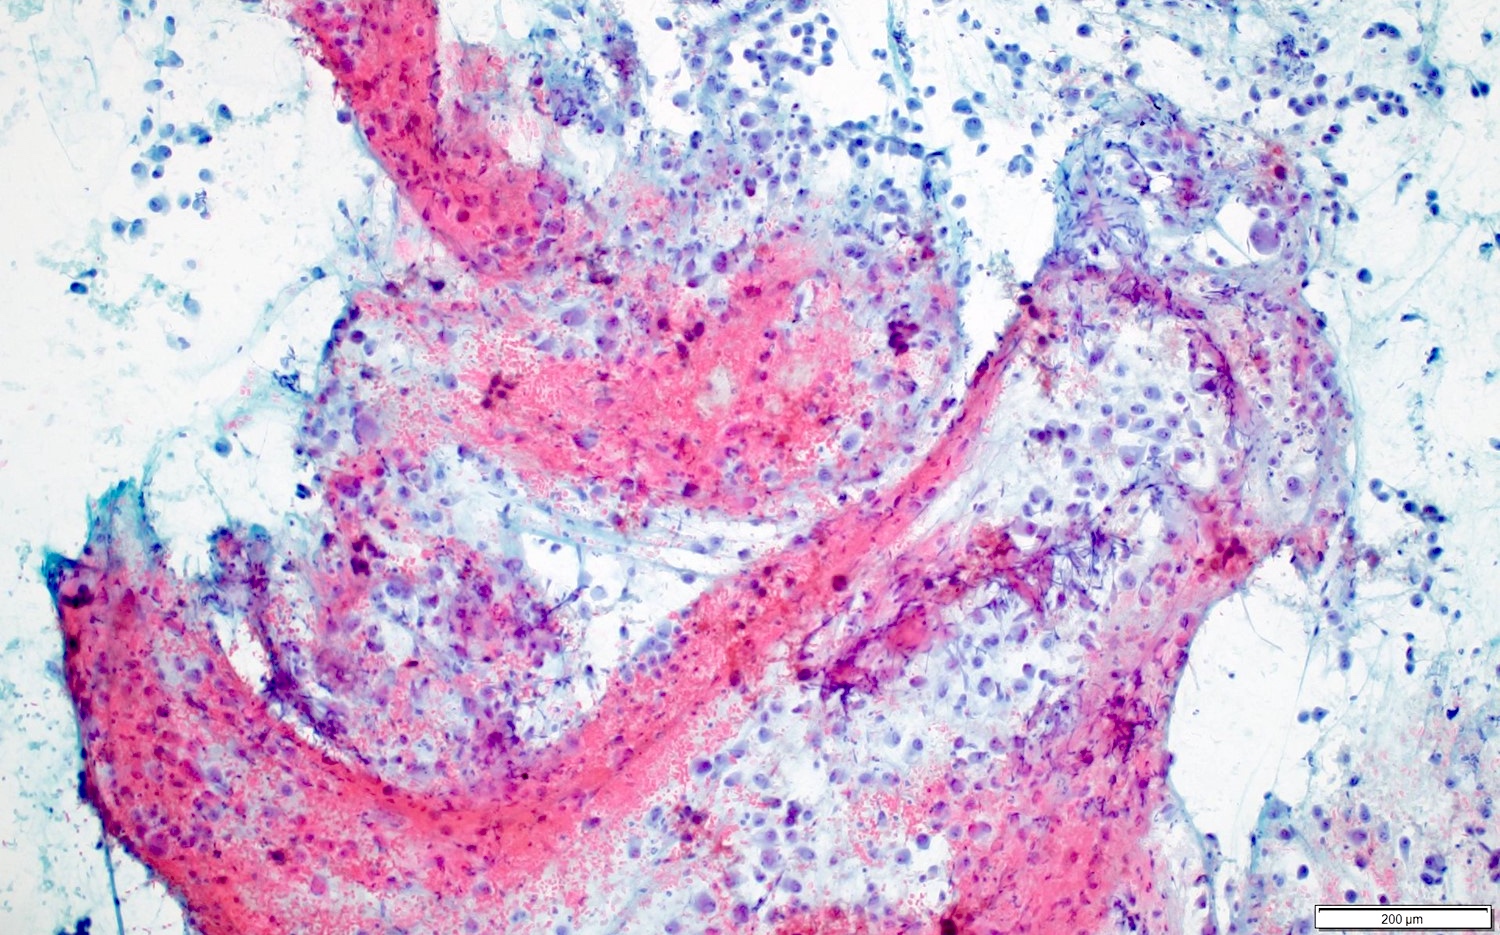

- 2 main histologic growth patterns were described (Am J Surg Pathol 2019;43:581)

- Non-mass forming

- Sinusoidal

- Dilated sinusoids lined by atypical endothelial cells seen in angiosarcoma with hyperchromatic nuclei

- Peliotic

- Blood pools and fibrin surrounded by hepatocytes

- Peripheral clusters of atypical endothelial cells seen in angiosarcoma mixed with inflammatory cells may extend into the sinusoids

- Mass forming

- Vasoformative shows architectural complexity and interconnecting vascular channels

- Anastomosing vessels and haphazard vascular channels

- Endothelial cells show tufting, atypia and mitotic figures

- Nonvasoformative shows epithelioid to spindled morphology

- Epithelioid morphology (epithelioid angiosarcoma) is most common (Am J Surg Pathol 2004;28:298)

- Solid nests or sheets of tumor cells

- Tumor often invades into sinusoids and hepatic venules at the periphery

- Cells have eosinophilic cytoplasm and oval nuclei

- Chromatin can be vesicular

- Multinucleated giant cells can be present

- Unusual growth patterns (Am J Surg Pathol 2019;43:581)

- Whorls of spindle cells in a background of chronic inflammation and loose myxoid to sclerotic stroma

- Infantile hemangioma-like angiosarcoma

- Hemangioma-like angiosarcoma

Microscopic (histologic) images